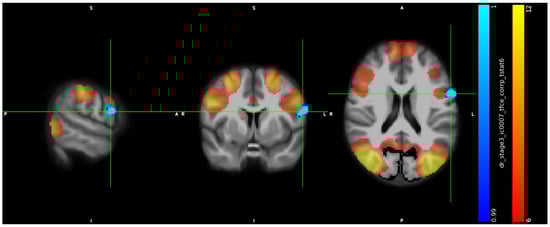

3.2. IC Analysis and Dual Regression

3.3. Neuropsychological Data

3.4. ICA, Neuropsychological Data, and Hormones